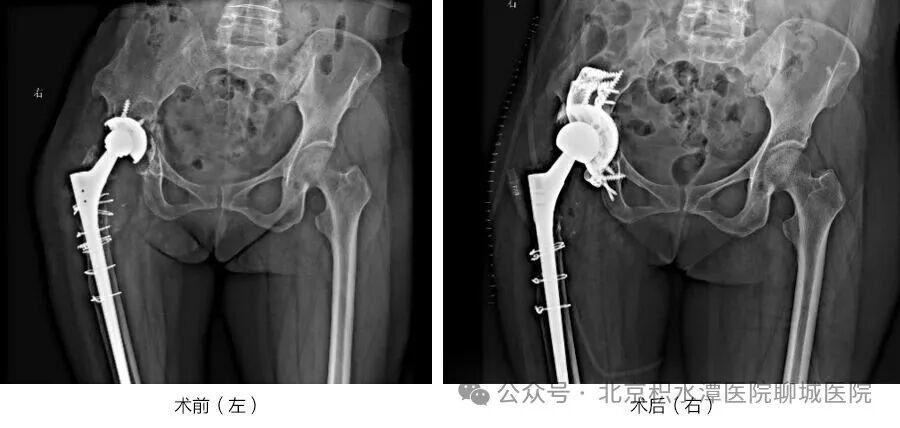

近日,61岁的宁夏中卫患者王先生,在家人的搀扶下缓缓走出北京积水潭医院聊城医院病房。他稳稳迈出右腿,感受着三十余年来从未有过的髋关节轻松感,脸上终于露出释然的笑容。这一步,他在病痛中煎熬了四年,更在全国多家医院的婉拒中等待了一年。 王先生有着长达三十余年的髋关节病史,曾经历两次髋部手术。近四年来,他的右髋疼痛反复发作,行走功能严重受限,日常起居都需家人照料。一年前,CT检查确诊其为“右髋关节置换术后髋臼假体周围骨折并假体松动”,这一诊断让他辗转宁夏、陕西、甘肃等多地医院,却因手术涉及“髋臼骨缺损Paprosky III型”这一关节外科领域的高难度病变——髋臼骨量严重丢失,常规假体无法固定,且合并骨盆横断骨折,多家医院均未获得理想治疗方案。偶然间,王先生得知作为国家区域医疗中心医院的北京积水潭医院聊城医院,在复杂关节疾病诊疗领域实力雄厚,慕名来到徐辉副院长的门诊。 接诊后,医院高度重视,立即启动多学科协作机制。关节外科、麻醉科、创伤骨科专家迅速集结,共同对王先生的病情展开全面评估。考虑到病情的复杂性与手术的高风险性,团队决定引入创新技术——借助3D打印技术精准复制患者髋臼模型,通过术前模拟反复推敲手术细节,最终确定了“髋臼后柱钢板固定+髋臼三翼加强杯联合植骨”的个性化重建方案,这一方案也成为全省首例采用该组合技术治疗Paprosky III型髋臼骨缺损的案例。 手术当日,在麻醉团队的严密监测与保障下,关节外科徐辉院长主刀施治。术中,团队精准取出松动假体,细致清理瘢痕组织;创伤骨科副主任李浩随后完成髋臼后柱固定,将3D打印定制的髋臼加强杯精准植入骨缺损区域,同步进行植骨操作;最后顺利安装新型股骨头假体,并反复测试关节活动度与稳定性。整台手术历时仅2.5小时,出血少、视野清,各项指标均完美达到预期。 此次高难度手术的成功,不仅彰显了北京积水潭医院聊城医院作为国家区域医疗中心医院的技术引领作用,更体现了创新技术与多学科协作在攻克疑难重症中的关键价值。目前,北京积水潭医院聊城医院服务范围已扩展至全国29个省份,累计为数百名跨省患者解决了骨科、烧伤科疾病困扰,用精湛医术与暖心服务搭建起跨越千里的健康桥梁,为更多患者的康复之路点亮了希望。